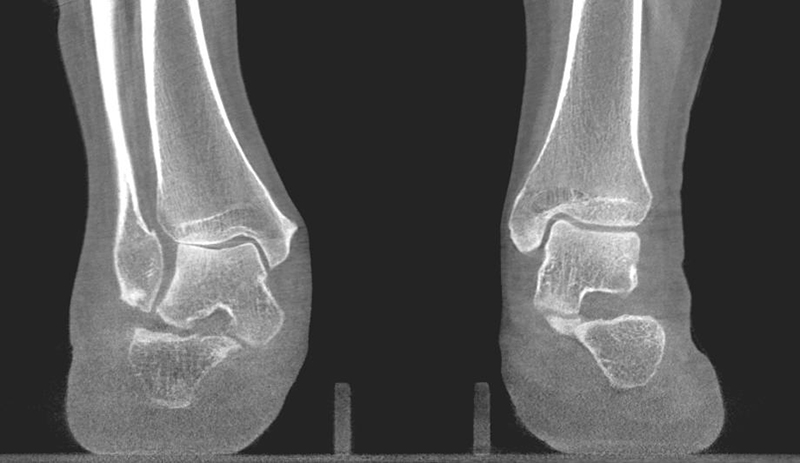

In den letzten Jahren hat die digitale Volumen Tomografie (DVT) erheblich an Bedeutung gewonnen. Der Vorteil dieses Verfahrens ist eine computertomografieartige Abbildung unter Vollbelastung des Fußes mit der Möglichkeit einer 3-D Rekonstruktion. Verglichen zur Computertomografie hat die DVT eine deutlich geringere Strahlenbelastung 12. Aus dem Datensatz lassen sich Projektionsbilder errechnen, sodass viele belastete konventionelle Aufnahmen durch eine DVT überflüssig werden.

Zur Vollansicht und zum Lesen der Bildbeschreibung bitte das Bild anklicken.